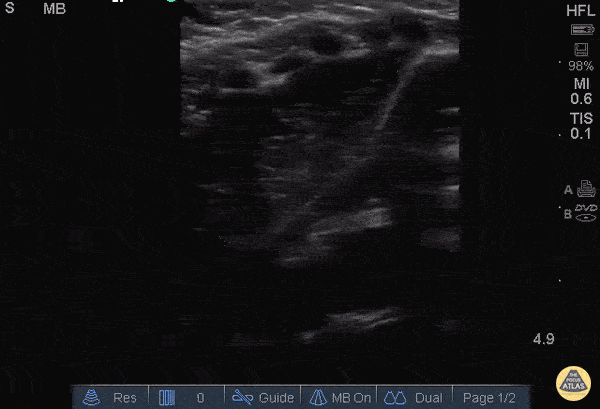

Example of a thymus that can often be confused for hepatization! Don’t make this mistake John F Kilpatrick - Kings County Hospital